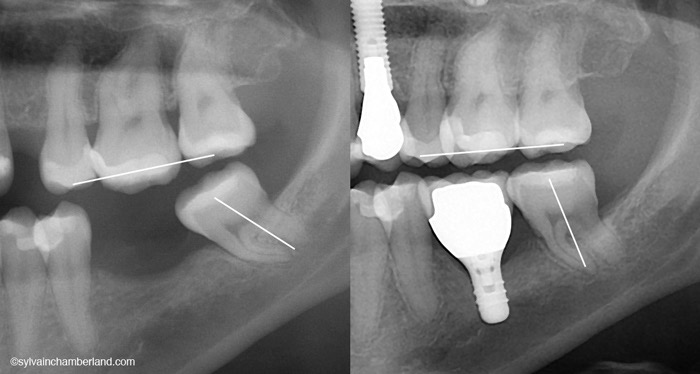

② 旁邊的牙齒可能原本就有輕微鬆動或傾斜

缺牙一段時間後,兩旁的牙齒常見:

• 往缺牙處傾斜

• 牙縫變大

• 牙周萎縮

這些問題在做完植牙後仍然存在。

即使植牙本身做得很好,旁邊的牙縫依舊會讓食物容易跑進去。